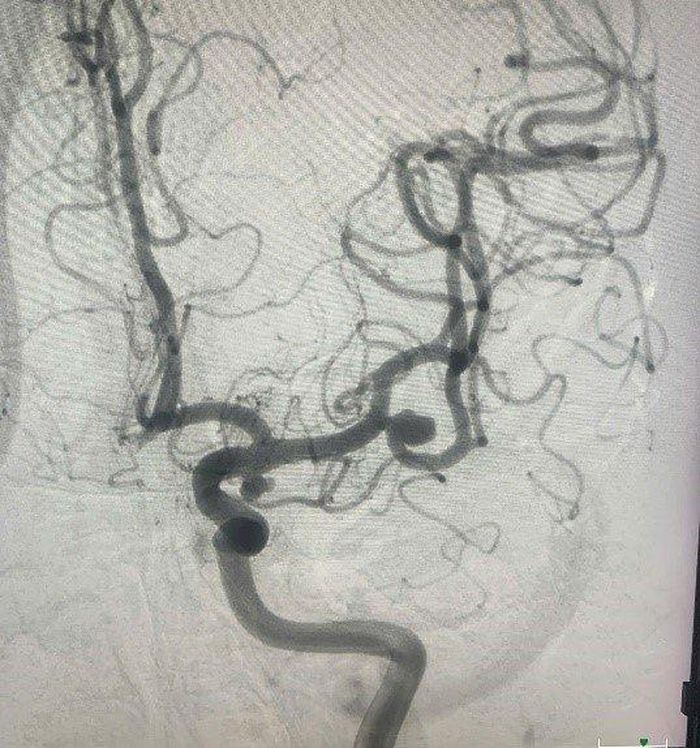

Khi chụp CT, bác sĩ phát hiện người đàn ông bị phình động mạch não, có khả năng vỡ cao, được nhập viện chờ can thiệp.

TS.BS Lương Tuấn Anh, Khoa Chẩn đoán và Can thiệp Tim mạch, Bệnh viện TWQĐ 108 cho biết, bệnh viện vừa tiếp nhận bệnh nhân P.V.D 58 tuổi (Hà Nội) vào Khoa Chẩn đoán và Can thiệp Tim mạch - Bệnh viện TWQĐ 108 vì đau đầu âm ỉ suốt 2 tuần, uống thuốc không hết đau. Kết quả chụp CT cho thấy bệnh nhân bị phình động mạch não, có khả năng vỡ cao nên bác sĩ cho nhập viện, chờ can thiệp nút túi phồng bằng lò xo kim loại.

Hình ảnh phình động mạch não.

Theo BS Lương Tuấn Anh, phình động mạch não là hiện tượng một đoạn mạch máu trong não có đường kính lớn hơn bình thường, xảy ra khi đoạn mạch máu yếu, bị phình dưới áp lực của dòng máu. Nếu không được phát hiện, điều trị, túi phồng sẽ tăng dần kích thước, vỡ, gây chảy máu dưới nhện (một dạng chảy máu não).

Can thiệp phồng động mạch não có nhiều phương pháp, bệnh nhân P.V.D đã được chọn kỹ thuật nút túi phồng bằng lò xo kim loại. Quá trình điều trị thuận lợi, bệnh nhân được ra viện sau 24h, trở lại cuộc sống bình thường.